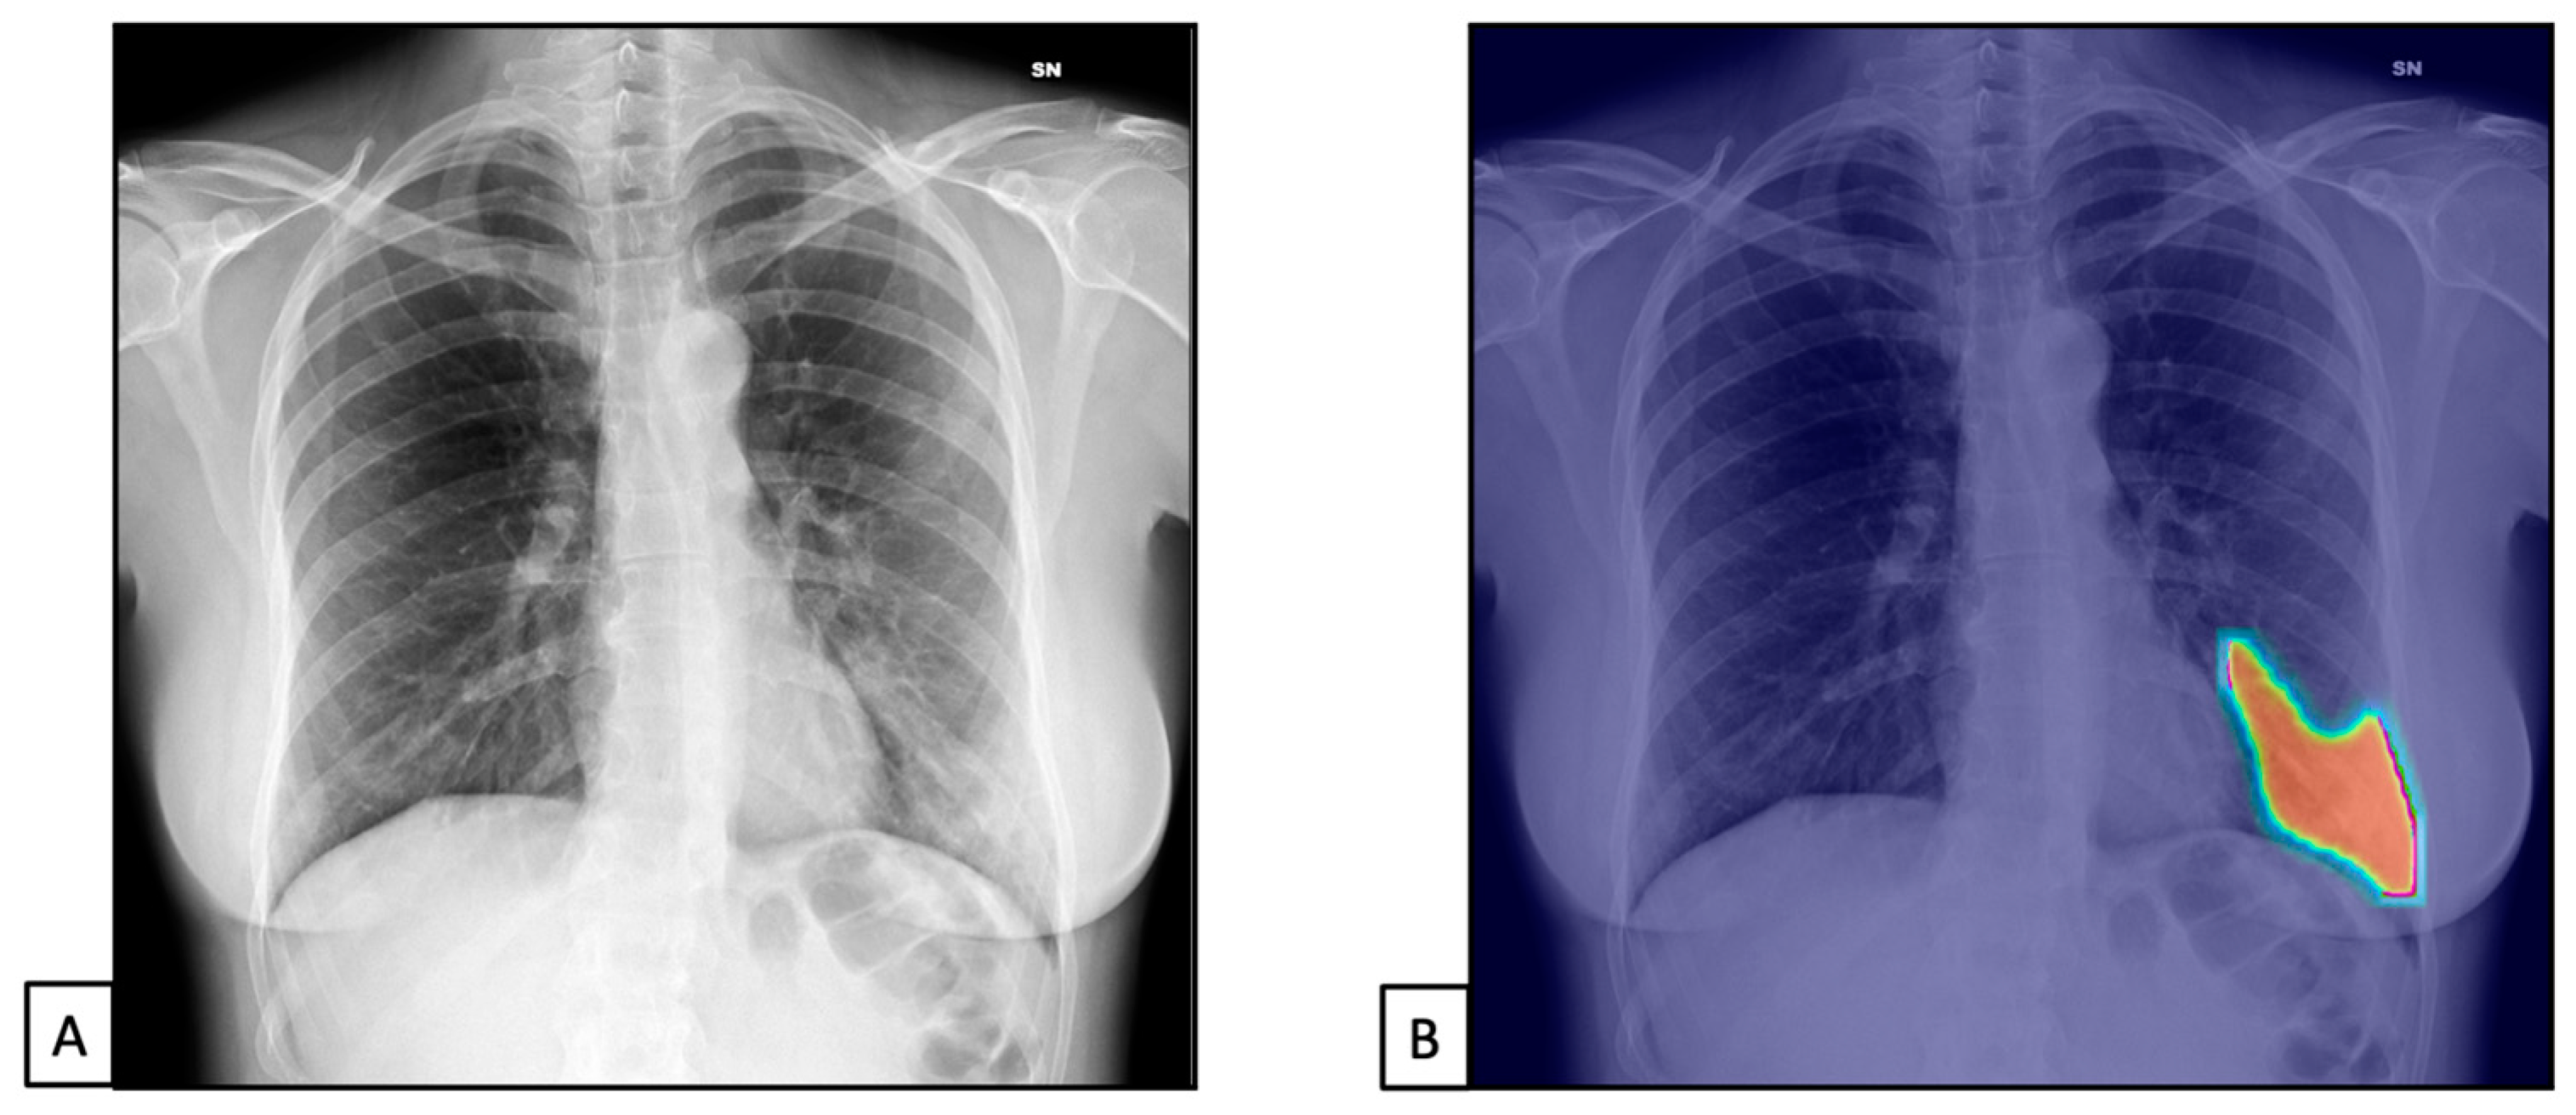

The TPs and TNs, according to the radiologist, were similar to the AI system ones [n = 1450 (67.8) and n = 503 (23.5), and n = 1419 (66.3) and n = 515 (24.1), respectively]. Similar results were found for FPs and FNs [n = 127 (5.9), n = 60 (2.8), n = 127 (5.9), and n = 79 (3.7), respectively]. This resulted in 96% sensitivity (95%CIs = 94.9–96.9) and 79.8% specificity (76.4–82.9) for the radiologist and 94.7% sensitivity (93.4–95.8) and 80.2% specificity (76.9–83.2) for the AI system (Figure 3). The radiologist showed 91.9% PPV (90.7–93.0) and 89.3% NPV (86.7–91.5), while the AI system showed 91.7% PPV (90.5–92.8) and 86.7% NPV (83.9–89.0).

Figure 3.

Chest X-rays of patients admitted to the emergency department with the suspicion of COVID-19 infection belonged to dataset 1. (A,C) represent CXRs acquired at the bedside, showing multiple slight interstitial and alveolar opacities located peripherally and with a lower distribution. (B,D) The AI system analysis obtained in a few seconds displays the pathological zones. The AI system reported a high suspicion of COVID-19 infection (99.99%). The final diagnosis was lung involvement by COVID-19 pneumonia.

Finally, the accuracy was similar between the radiologist and the AI system [91.2% (89.9–92.4) vs. 90.3% (89.0–91.6), respectively].